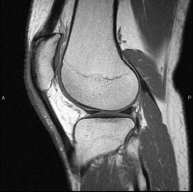

RM de Genoll

RM de GenollExploració per estudiar lesions a l'articulació, com trencaments dels meniscals i dels lligaments creuats (únicament es poden detectar amb aquesta prova), condropatia o desgast del cartílag i moltes altres alteracions derivades de l'activitat esportiva i dels canvis degeneratius (osteoartrosi). La durada aproximada és de 18 minuts. No utilitza radiació ionitzant.